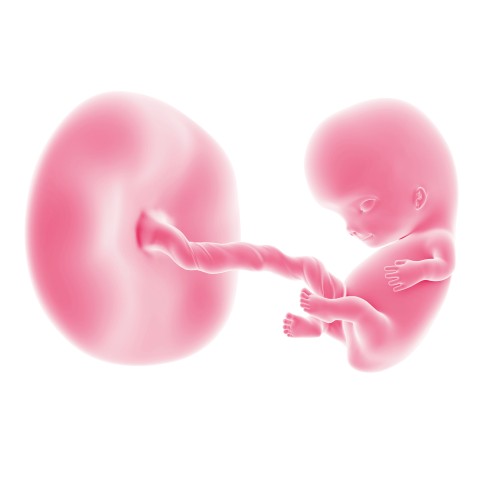

Третий месяц беременности начинается с 9 акушерской недели. В этот период в организме женщины активно происходит гормональная перестройка, а плод быстро развивается и увеличивается в размерах. Питание плода теперь осуществляется через плаценту, а не через стенки матки. Вероятность выкидыша на третьем месяце значительно снижается.

Объем амниотической жидкости, в которой находится малыш, на этом этапе составляет около 100 мл.

На девятой неделе беременности размер плода составляет примерно 22-33 мм. Он напоминает вишенку, а вес достигает 4 г. Плод начинает приобретать очертания человека: хвостик исчезает и превращается в копчик, конечности удлиняются, а черты лица становятся более выраженными. На коже малыша появляется легкий пушок.

На этой неделе плод активно шевелится: он может двигать руками и ногами, а также переворачиваться. Питание малыша обеспечивается плацентой, которая снабжает его кислородом и необходимыми питательными веществами.